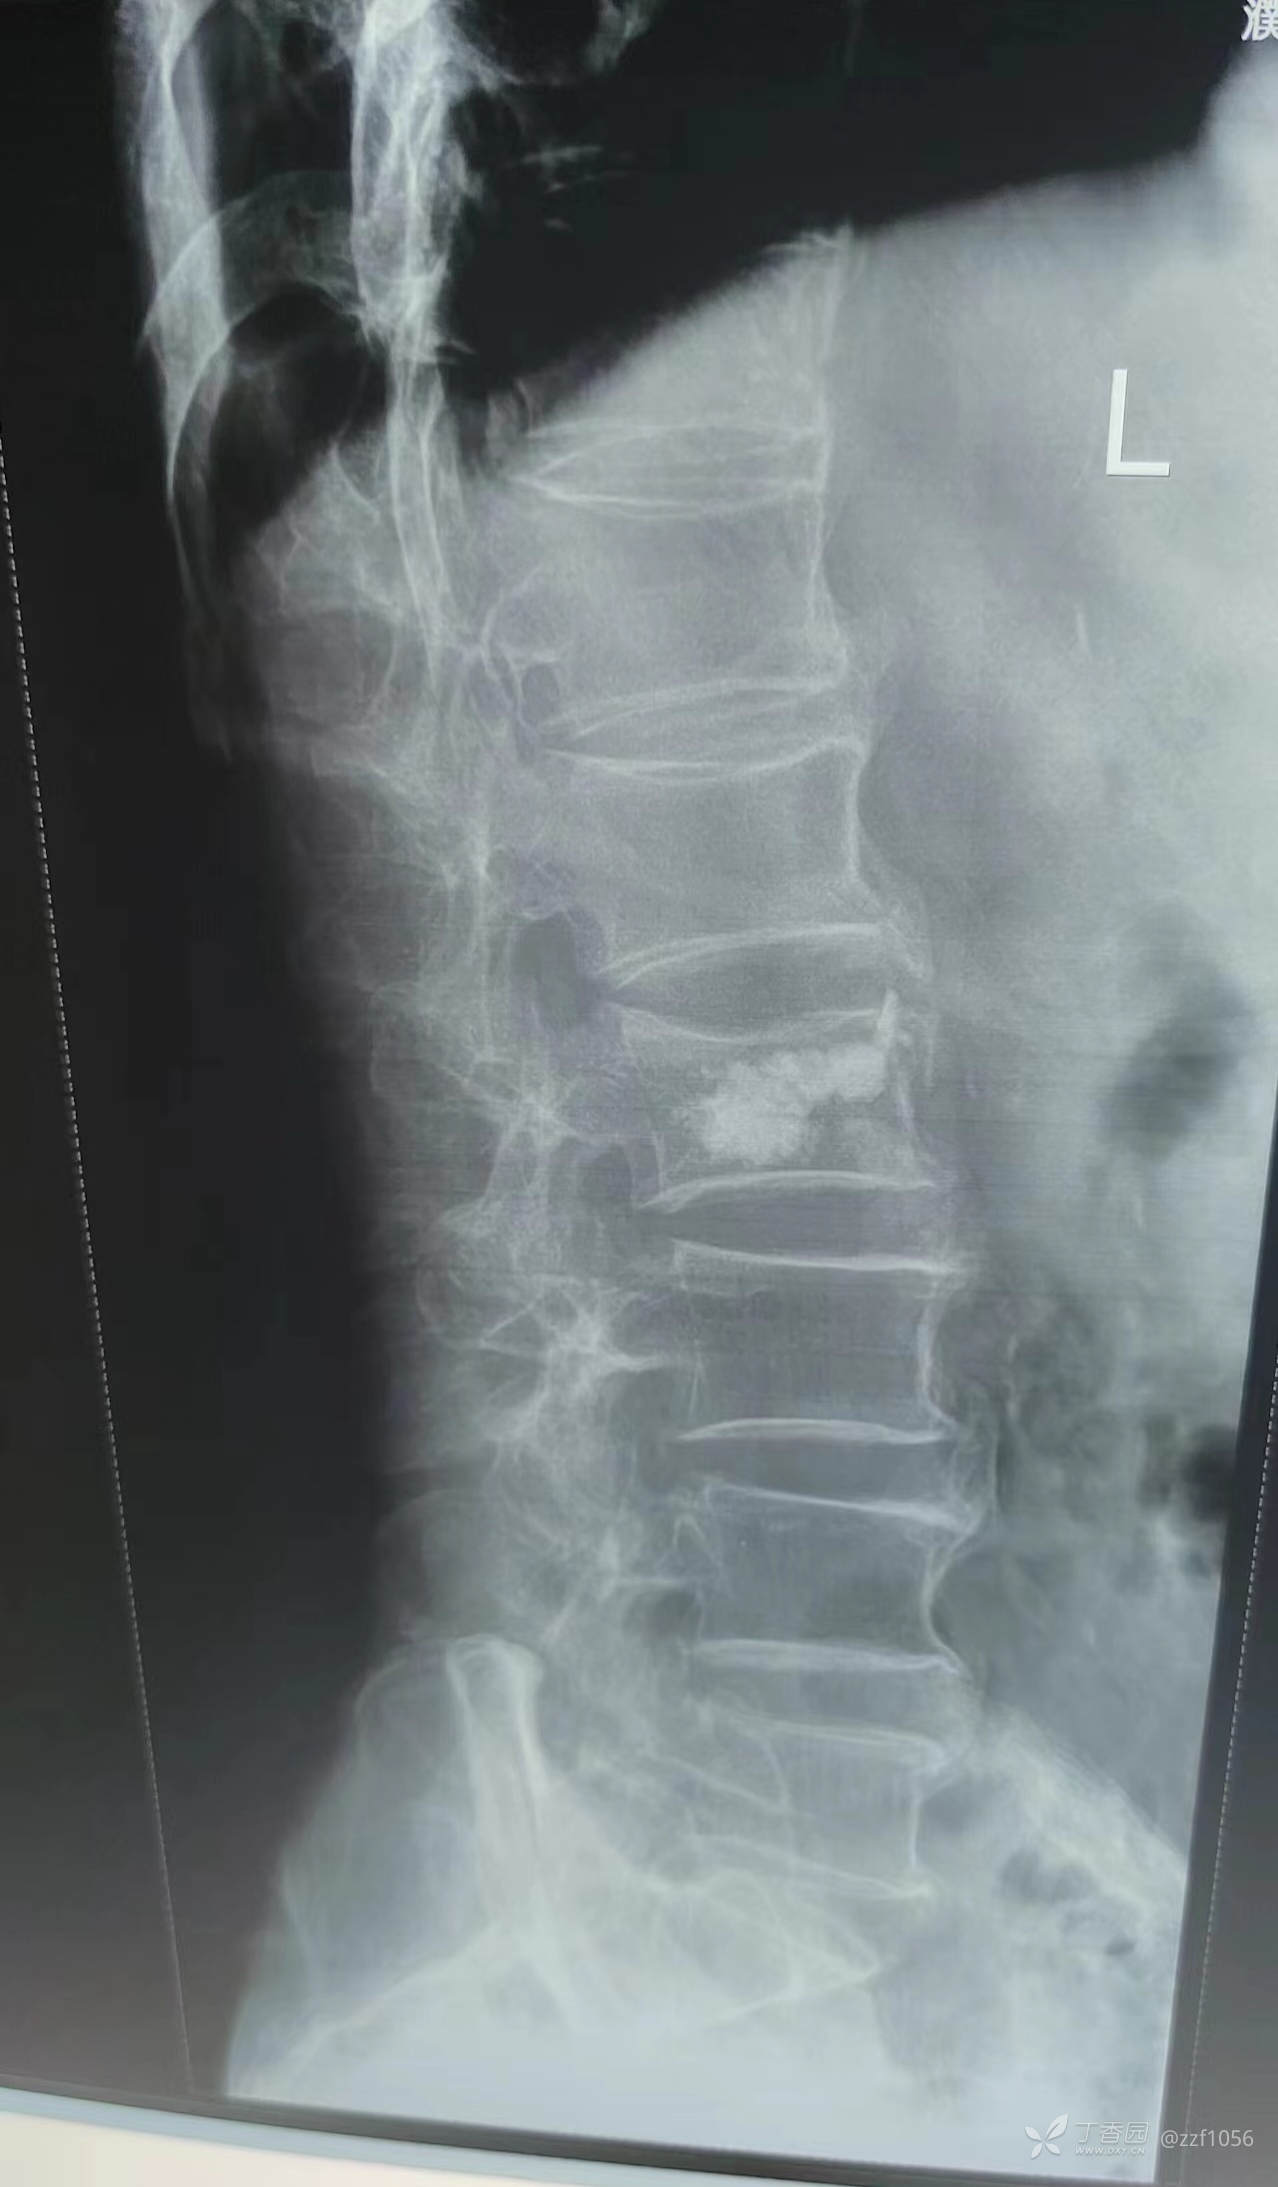

战友们觉得如何?骨髓泥量约3、4ml,那么单侧穿刺能否说的过去?

那么看术后CT

可是患者仍感觉腰痛,两个月后去B医院就诊,B医院观点是对侧再次穿刺加注骨水泥,站友们你的观点呢?

据病人描述加注后疼痛缓解